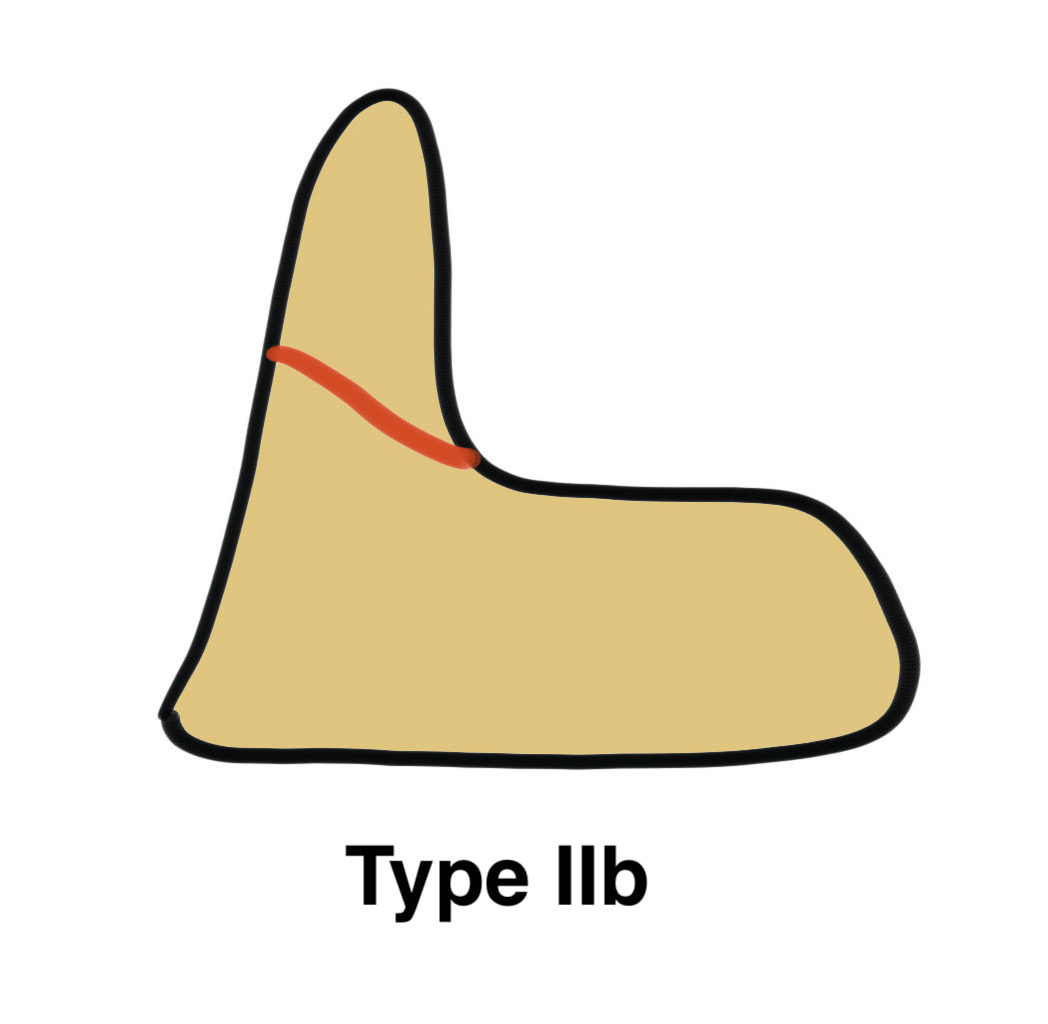

Grauer classification of Type II

| Type | Definition | Management |

| Type IIa |

Non or mimimally displaced No comminution |

Non operative treatment |

| Type IIb |

Displaced Fracture line anteror-superior to postero-inferior |

Potentially suitable for anterior odontoid screw |

| Type IIIc |

Displaced Fracture line antero-inferior to posteror-superior Significant comminution |

No suitable for screw Posterior fixation / fusion |